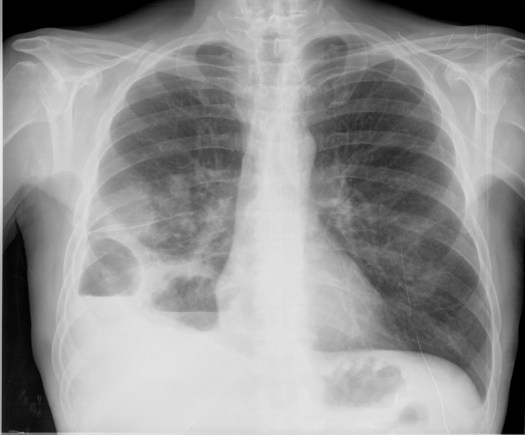

CASO: sospecha de neumonía.

Hallazgos:

- En un principio podríamos decir que existe un aumento de densidad retrocardiaco que podría ser compatible con condensación neumónica a dicho nivel, sin embargo estamos ante una placa poco inspirada, lo cual puede llevarnos a cometer errores diagnósticos.

- Se recomendó volver a realizar la radiografía, observar a continuación:

Ya no se observa el aumento de densidad retrocardiaco, la placa es normal.

INSPIRACIÓN: Una placa bien inspirada es aquella en la que se observar 6-7 arcos costales anteriores o 10-11 arcos costales posteriores. Lo contrario puede producir imágenes falsas de condensaciones o de seudocardiomegalia.